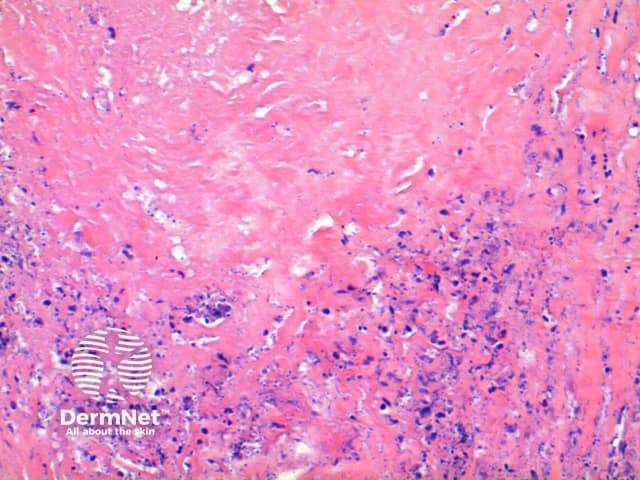

Figure 2

Mucin stains such as colloidal iron and alcian blue may be used to highlight the increased connective tissue mucins.